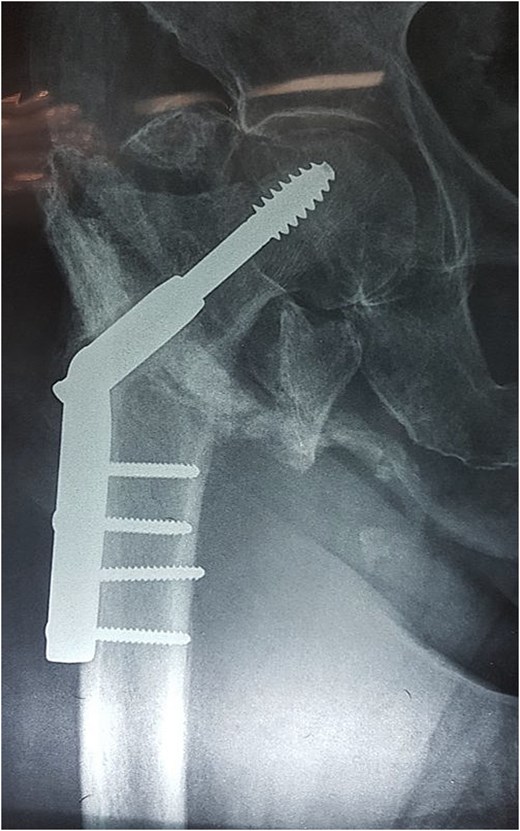

Radiographs of the right hip demonstrated a previously treated intertrochanteric fracture with dynamic hip screw fixation. Two screws were observed protruding beyond the medial cortex of the femur (Fig. 2).

Plain radiograph of the right hip. Intertrochanteric femoral fracture previously treated with dynamic hip screw and plate fixation. Two cortical screws are visible protruding beyond the medial cortex of the femur, representing the probable mechanism of vascular injury.